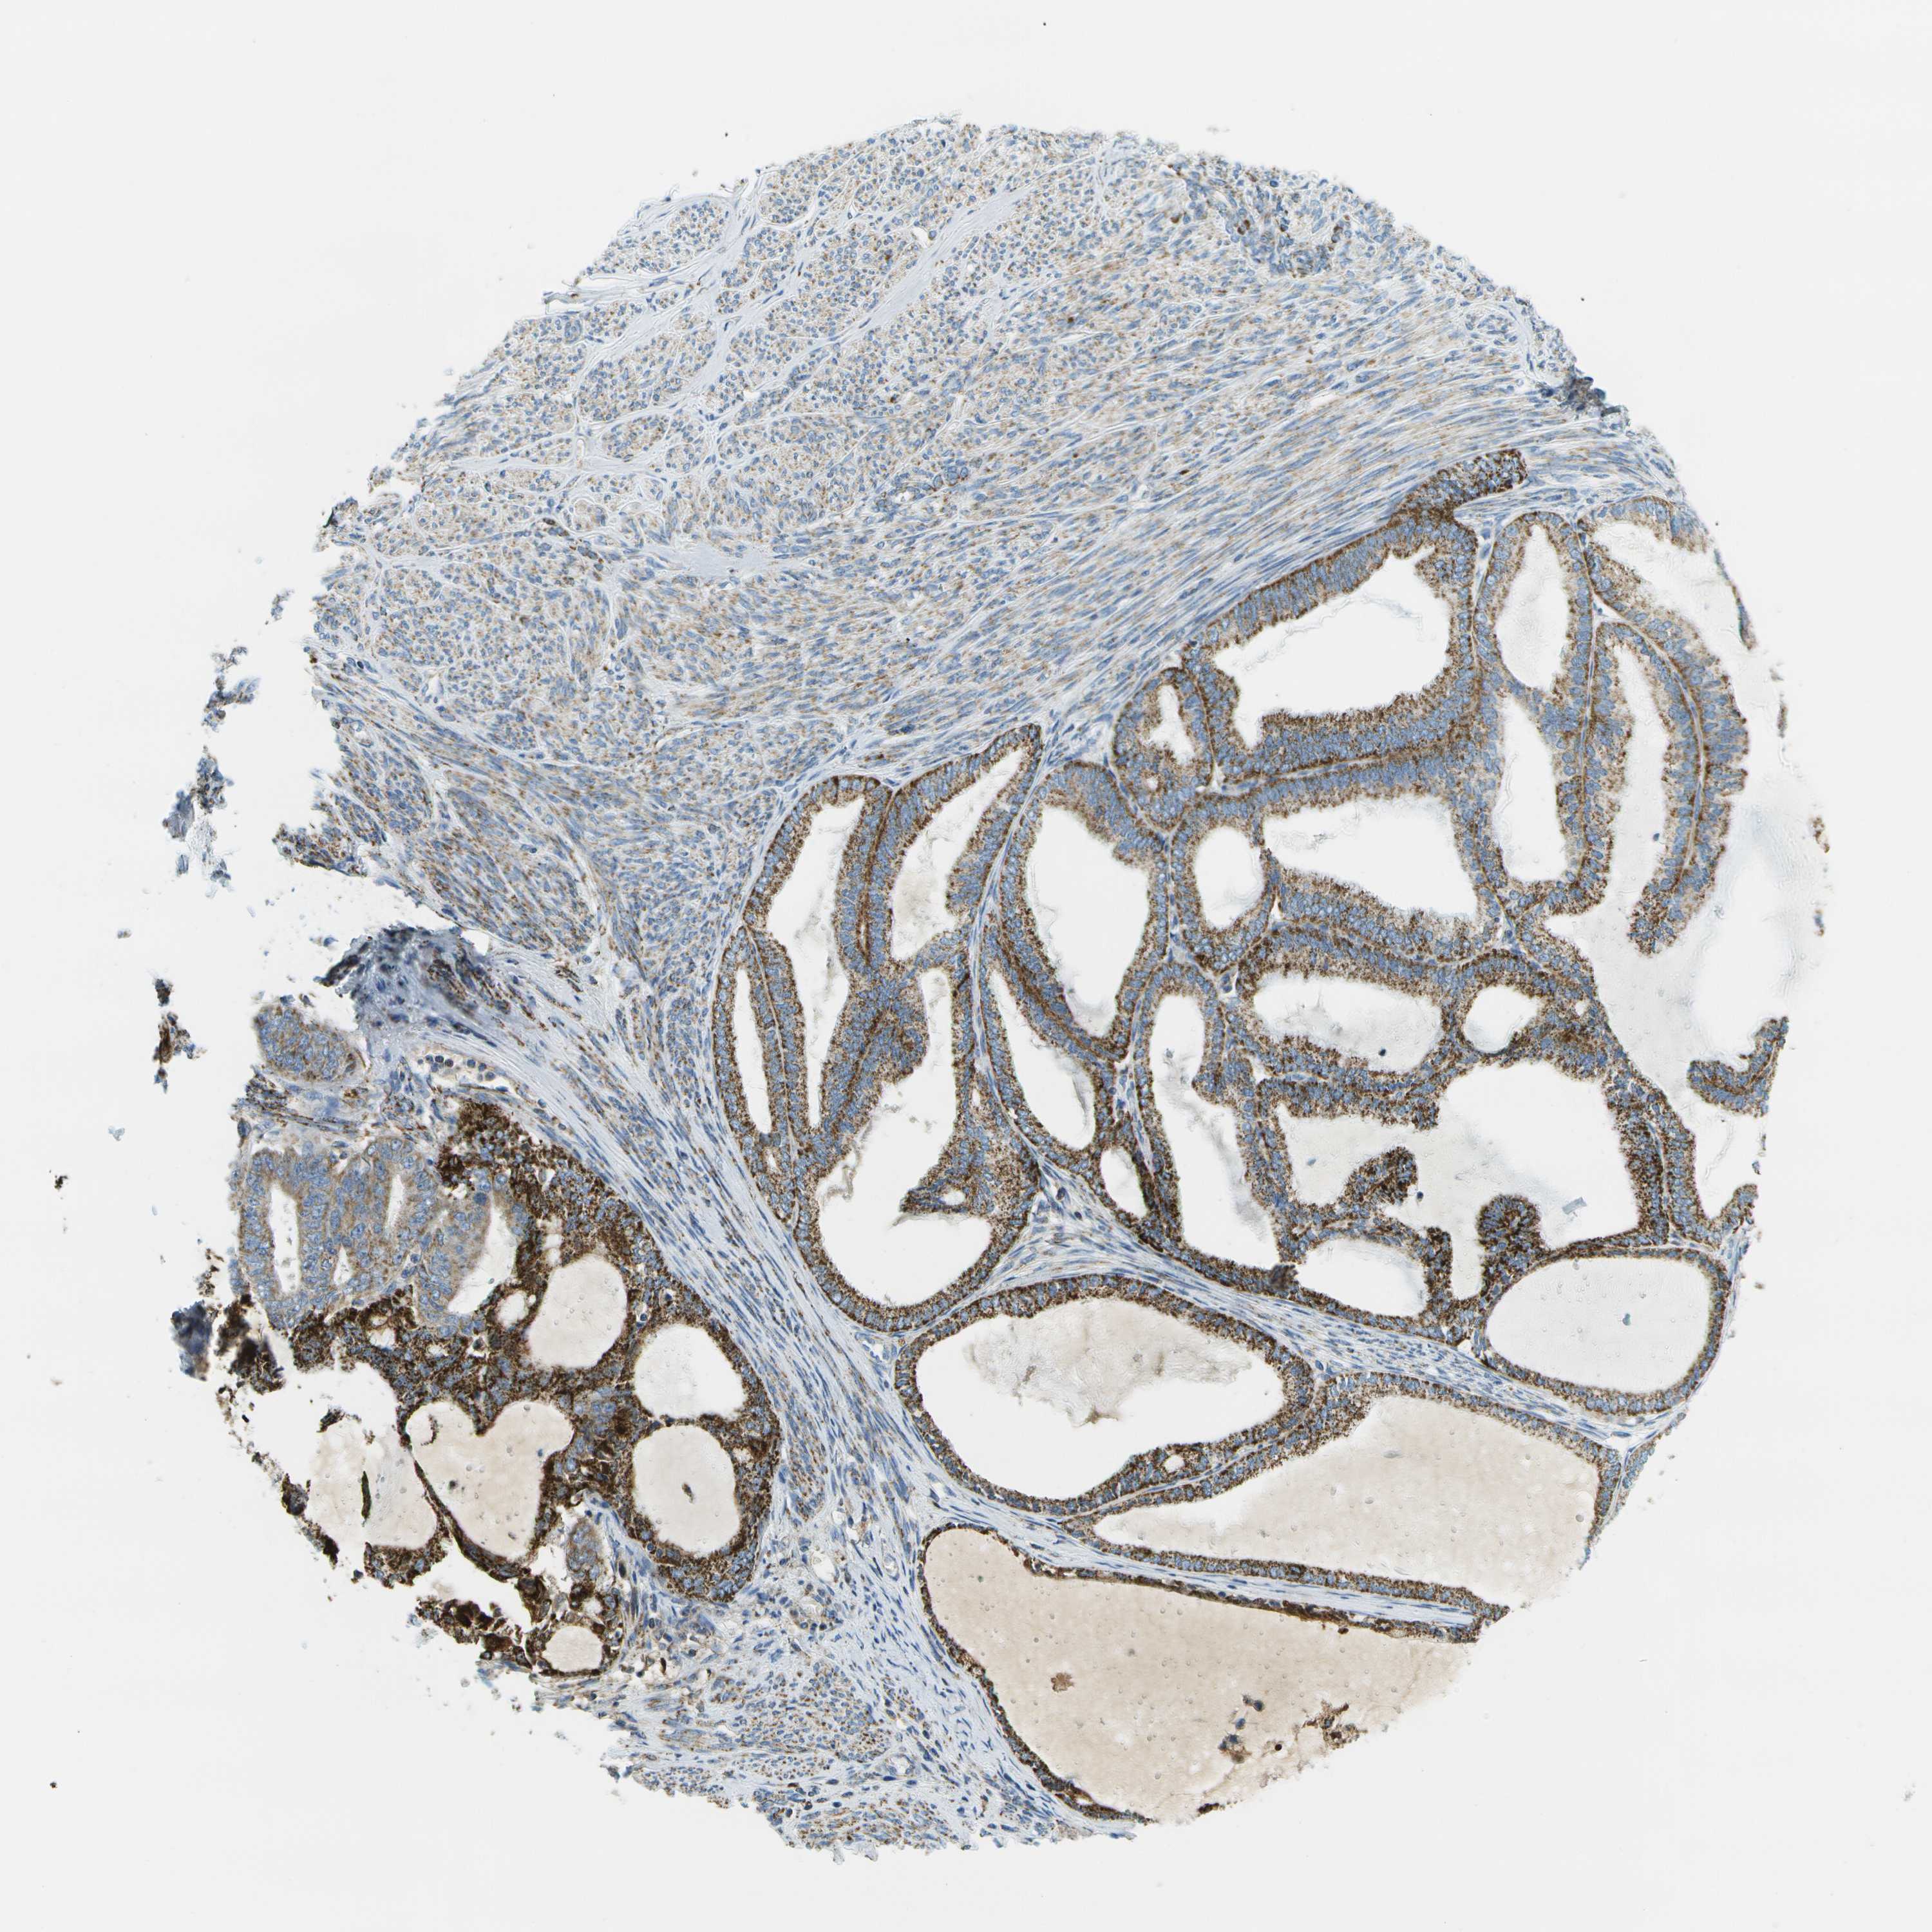

ENDOMETRIAL CANCER - Protein expressioni

A mouse-over function shows sample information and annotation data. Click on an image to view it in a full screen mode. Samples can be filtered based on level of antibody staining by selecting one or several of the following categories: high, medium, low and not detected. The assay and annotation is described here.

Note that samples used for immunohistochemistry by the Human Protein Atlas do not correspond to samples in the TCGA dataset.

Antibody stainingi

Antibody staining in the annotated cell types in the current human tissue is reported as not detected, low, medium, or high, based on conventional immunohistochemistry profiling in selected tissues. This score is based on the combination of the staining intensity and fraction of stained cells.

Each image is clickable and will lead to virtual microscopy that enables deeper exploration of all samples and also displays staining intensity scores, fraction scores and subcellular localization as well as patient and tissue information for each sample.

Antibody HPA017379

Staining

High

Medium

Low

Not detected

Intensity

Strong

Moderate

Weak

Negative

Quantity

>75%

75%-25%

<25%

None

Location

Nuclear

Cytoplasmic/membranous

Cytoplasmic/membranous,nuclear

Adenocarcinoma, NOS